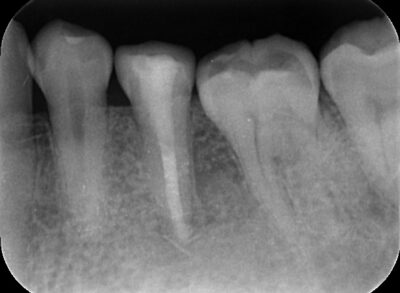

虫歯の最終形態、難治性根尖性歯周炎から歯を救う「歯根端切除術」や、グラグラの重度歯周病を改善する「歯周組織再生治療」など、世界基準の先進医療を日々実践しています。